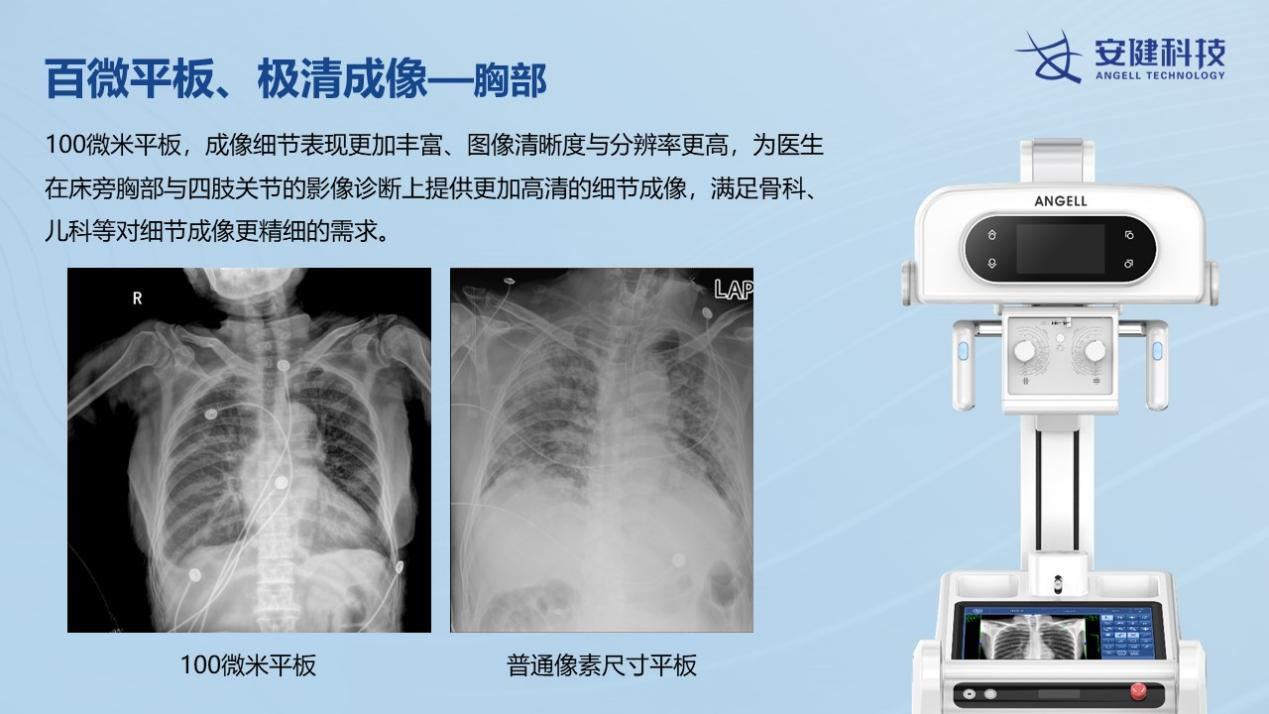

安健科技最新一代移動DR—飛燕Ⅱ,是國內首款大尺寸100微米超高清成像移動DR設備,具有1800萬像素的超高分辨率,讓床旁攝影的影像質量全面邁入高清時代。圖像質量不僅遠超當前市場上的移動DR設備,也遠超過當前大部分固定DR設備的圖像質量。

相較于普通DR的百萬攝影像素,近2000萬的高清像素,可以極大的提升床旁檢查效率,包括骨科、新生兒科、心臟外科、重癥監護科、急診科等患者的快速檢查。相較于目前市面上的低像素移動DR設備,100微米平板移動DR,在圖像的分辨率、寬容度上都全面優于常規的130微米左右的移動DR設備。